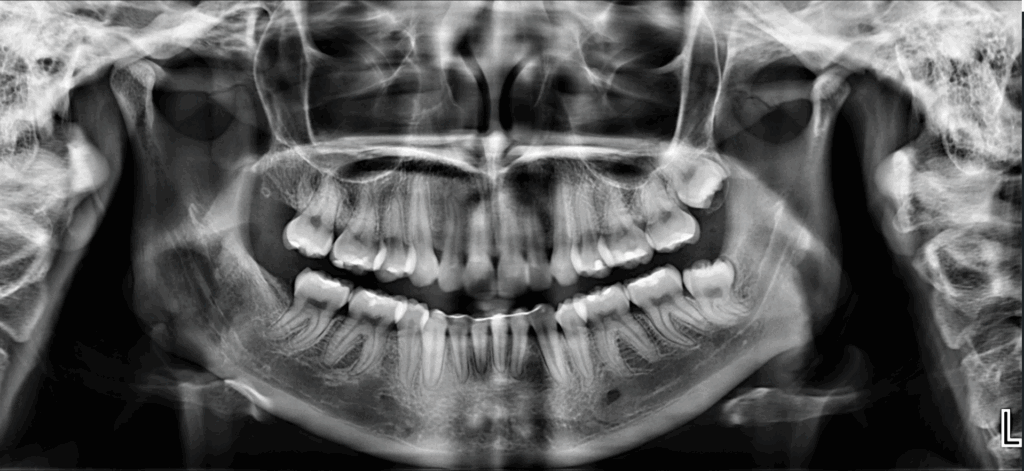

Paciente femenino de 27 años acude a IDM- Sede Jesús María con motivo de consulta para control de ortodoncia y a la evaluación de la radiografía panorámica se observa neumatización de ambos senos maxilares, múltiples restauraciones coronarias, dispositivo de ferulización anteroinferior, la ausencia de las piezas 18 y 48, la retención de la pieza 28 y de la pieza 48 que a su vez presenta una raíz supernumeraria y dilaceración hacia distal.

Radiografia Panorámica